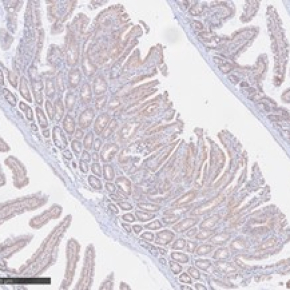

Une étude publiée dans Cell Death and Differentiation révèle que la protéine SLAP joue un rôle clé de suppresseur de tumeur dans le cancer colorectal. En inhibant le complexe mTORC2, un acteur clé de la croissance et de la dissémination tumorales, SLAP limite la prolifération et les capacités invasives des cellules cancéreuses colorectales. La perte de SLAP rend les tumeurs les plus agressives, mais également plus sensibles aux traitements ciblant la kinase mTOR, ouvrant de nouvelles perspectives thérapeutiques.